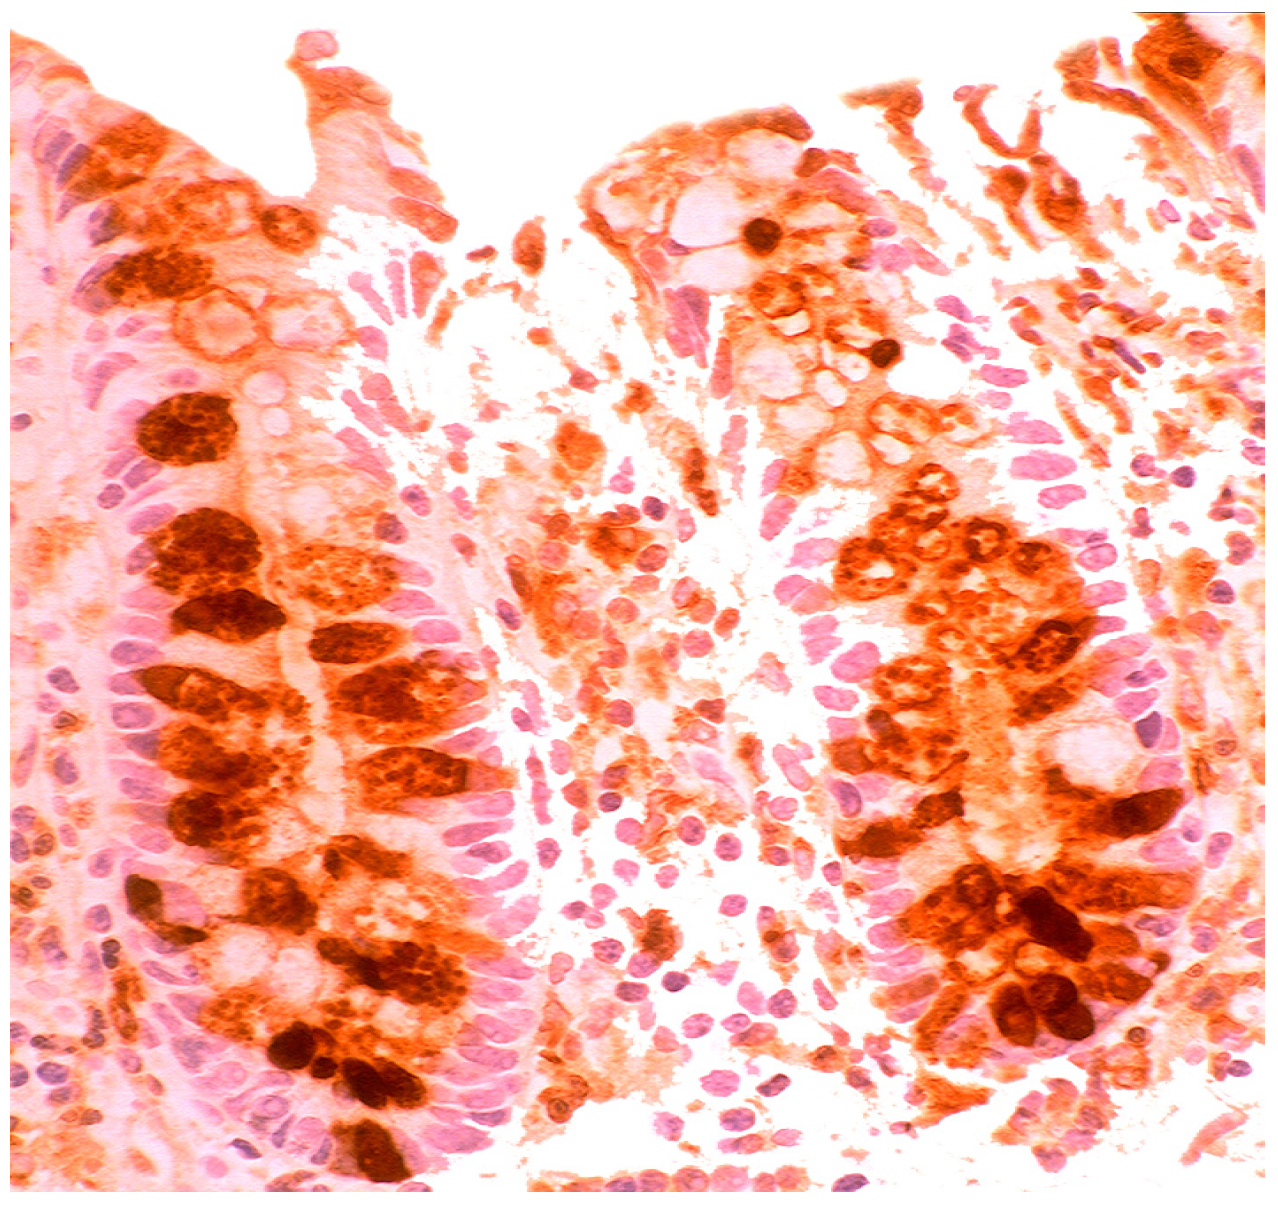

In the normal duodenal mucosa, Paneth cells produce lysozyme. In coeliac disease, lysozyme is up-regulated in goblet cells, in dilated crypts with mucus-metaplasia (Figure 9), a phenomenon more apparent in the bulbus [10] (Figure 10). It is not inconceivable that the lysozyme-rich mucus metaplasia mirror stem cell adaptation to the signals generated by the pathogenic bacteria present in the duodenal microenvironment [63].

Figure 9. Chronic atrophic duodenitis (celiac disease). Villous atrophy showing lysozyme-rich mucus metaplasia in the lower part of the crypts. Note lysozyme expressing goblet cells (lysozyme immunostain, ×10).